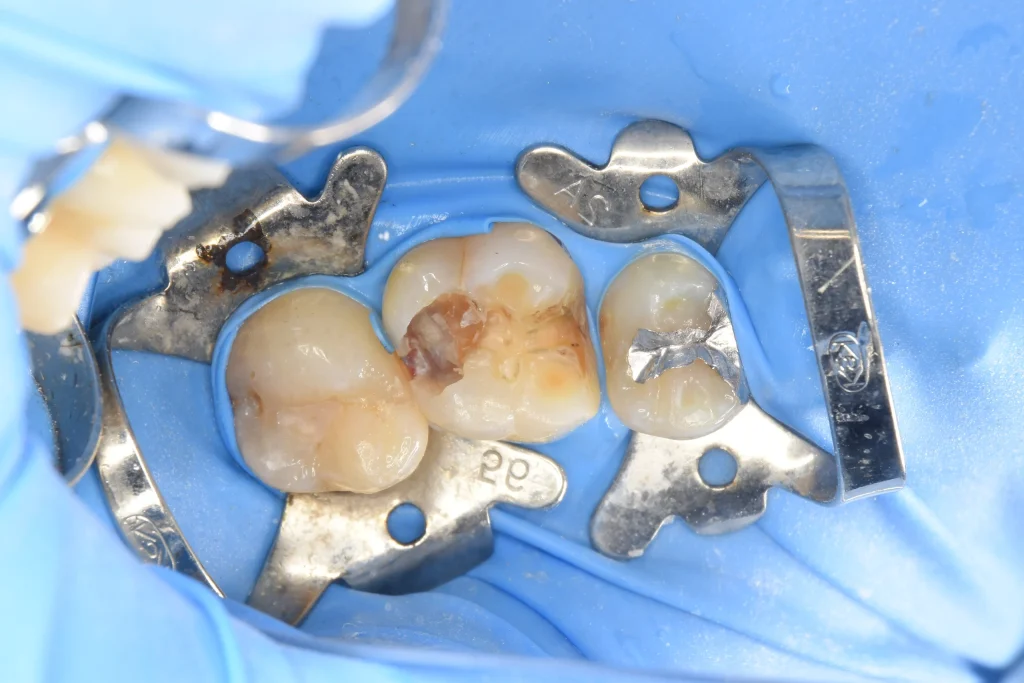

詰め物を外し、虫歯を明示しました。

虫歯を丁寧に除去し、神経まで虫歯が到達していたことがわかりました。